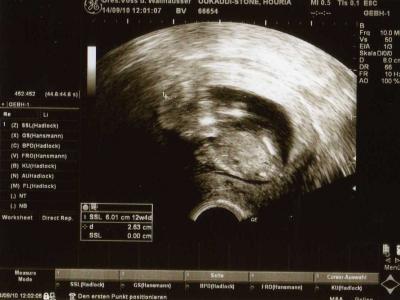

meinen krümmel gehts prima, ZU GUT !! meine FÄ wollte es messen, aber nein. es musste sich durchgehend bewegen also es misst jetzt gute 6cm vom scheitel bis zum steißbein. mit den beinchen gerechnet misst es sagenhafte 10cm. bin jetzt doch in der 12+4 ssw !! dieses bild ist das beste was sie machen konnte...

Bild zu BIN WIEDER DA !! - Forum für März - Mamis